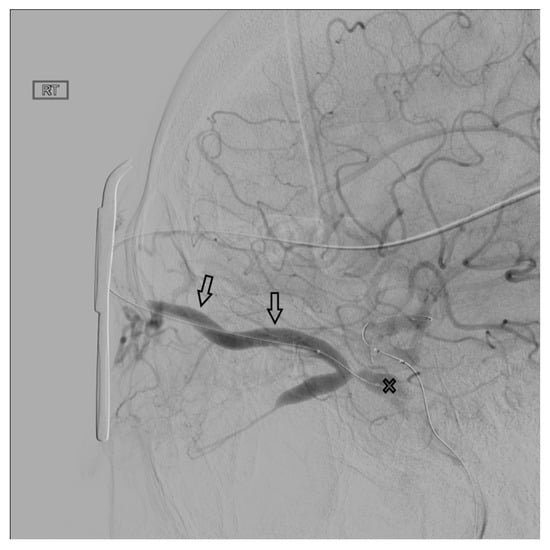

Figure 3. The middle temporal vein (solid arrow) and its connection (open arrow) with the SOV are demonstrated.